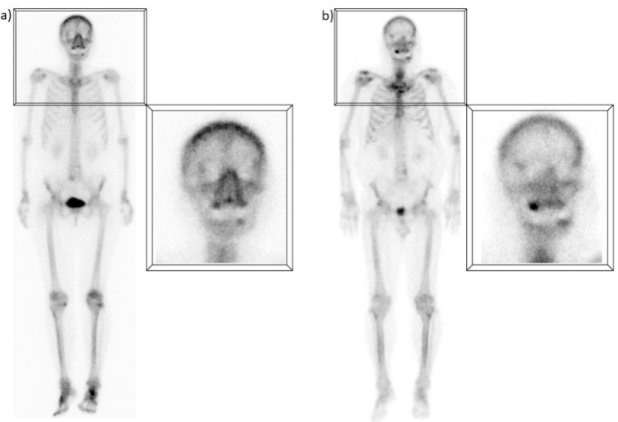

G) Captación mandibular

La captación focal en la mandíbula constituye otro hallazgo muy frecuente. Aunque se sabe que comúnmente representa la presencia de un proceso dental benigno, a menudo no se menciona en los reportes, o se describe como un hallazgo no específico o indeterminado. Corresponde habitualmente a procesos cicatrizales en sitios de extracción dental o implantes, así como a infecciones pulpares o periodontales (periodontitis) con cambios óseos u osteítis residual(14). La evolución en el tiempo ha sido descrita en algunos estudios como predictor de enfermedad periodontal grave e incluso de osteonecrosis de la mandíbula(15). Sólo en aproximadamente 1% de los casos esta captación representa una lesión benigna como odontoma o fibroma osificante y muy raramente podría estar relacionado con metástasis(16) (fig. 7).